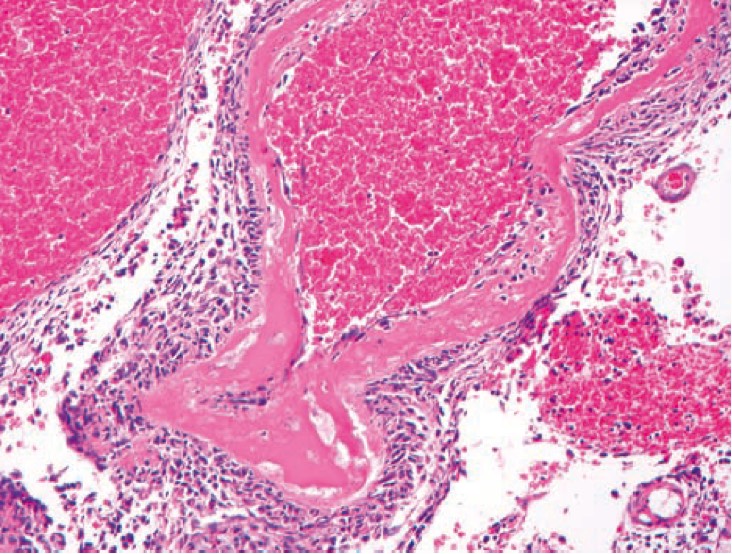

1031. Сосудистый паттерн повреждения в головном мозге, приведенный на микрофотографии, связан с